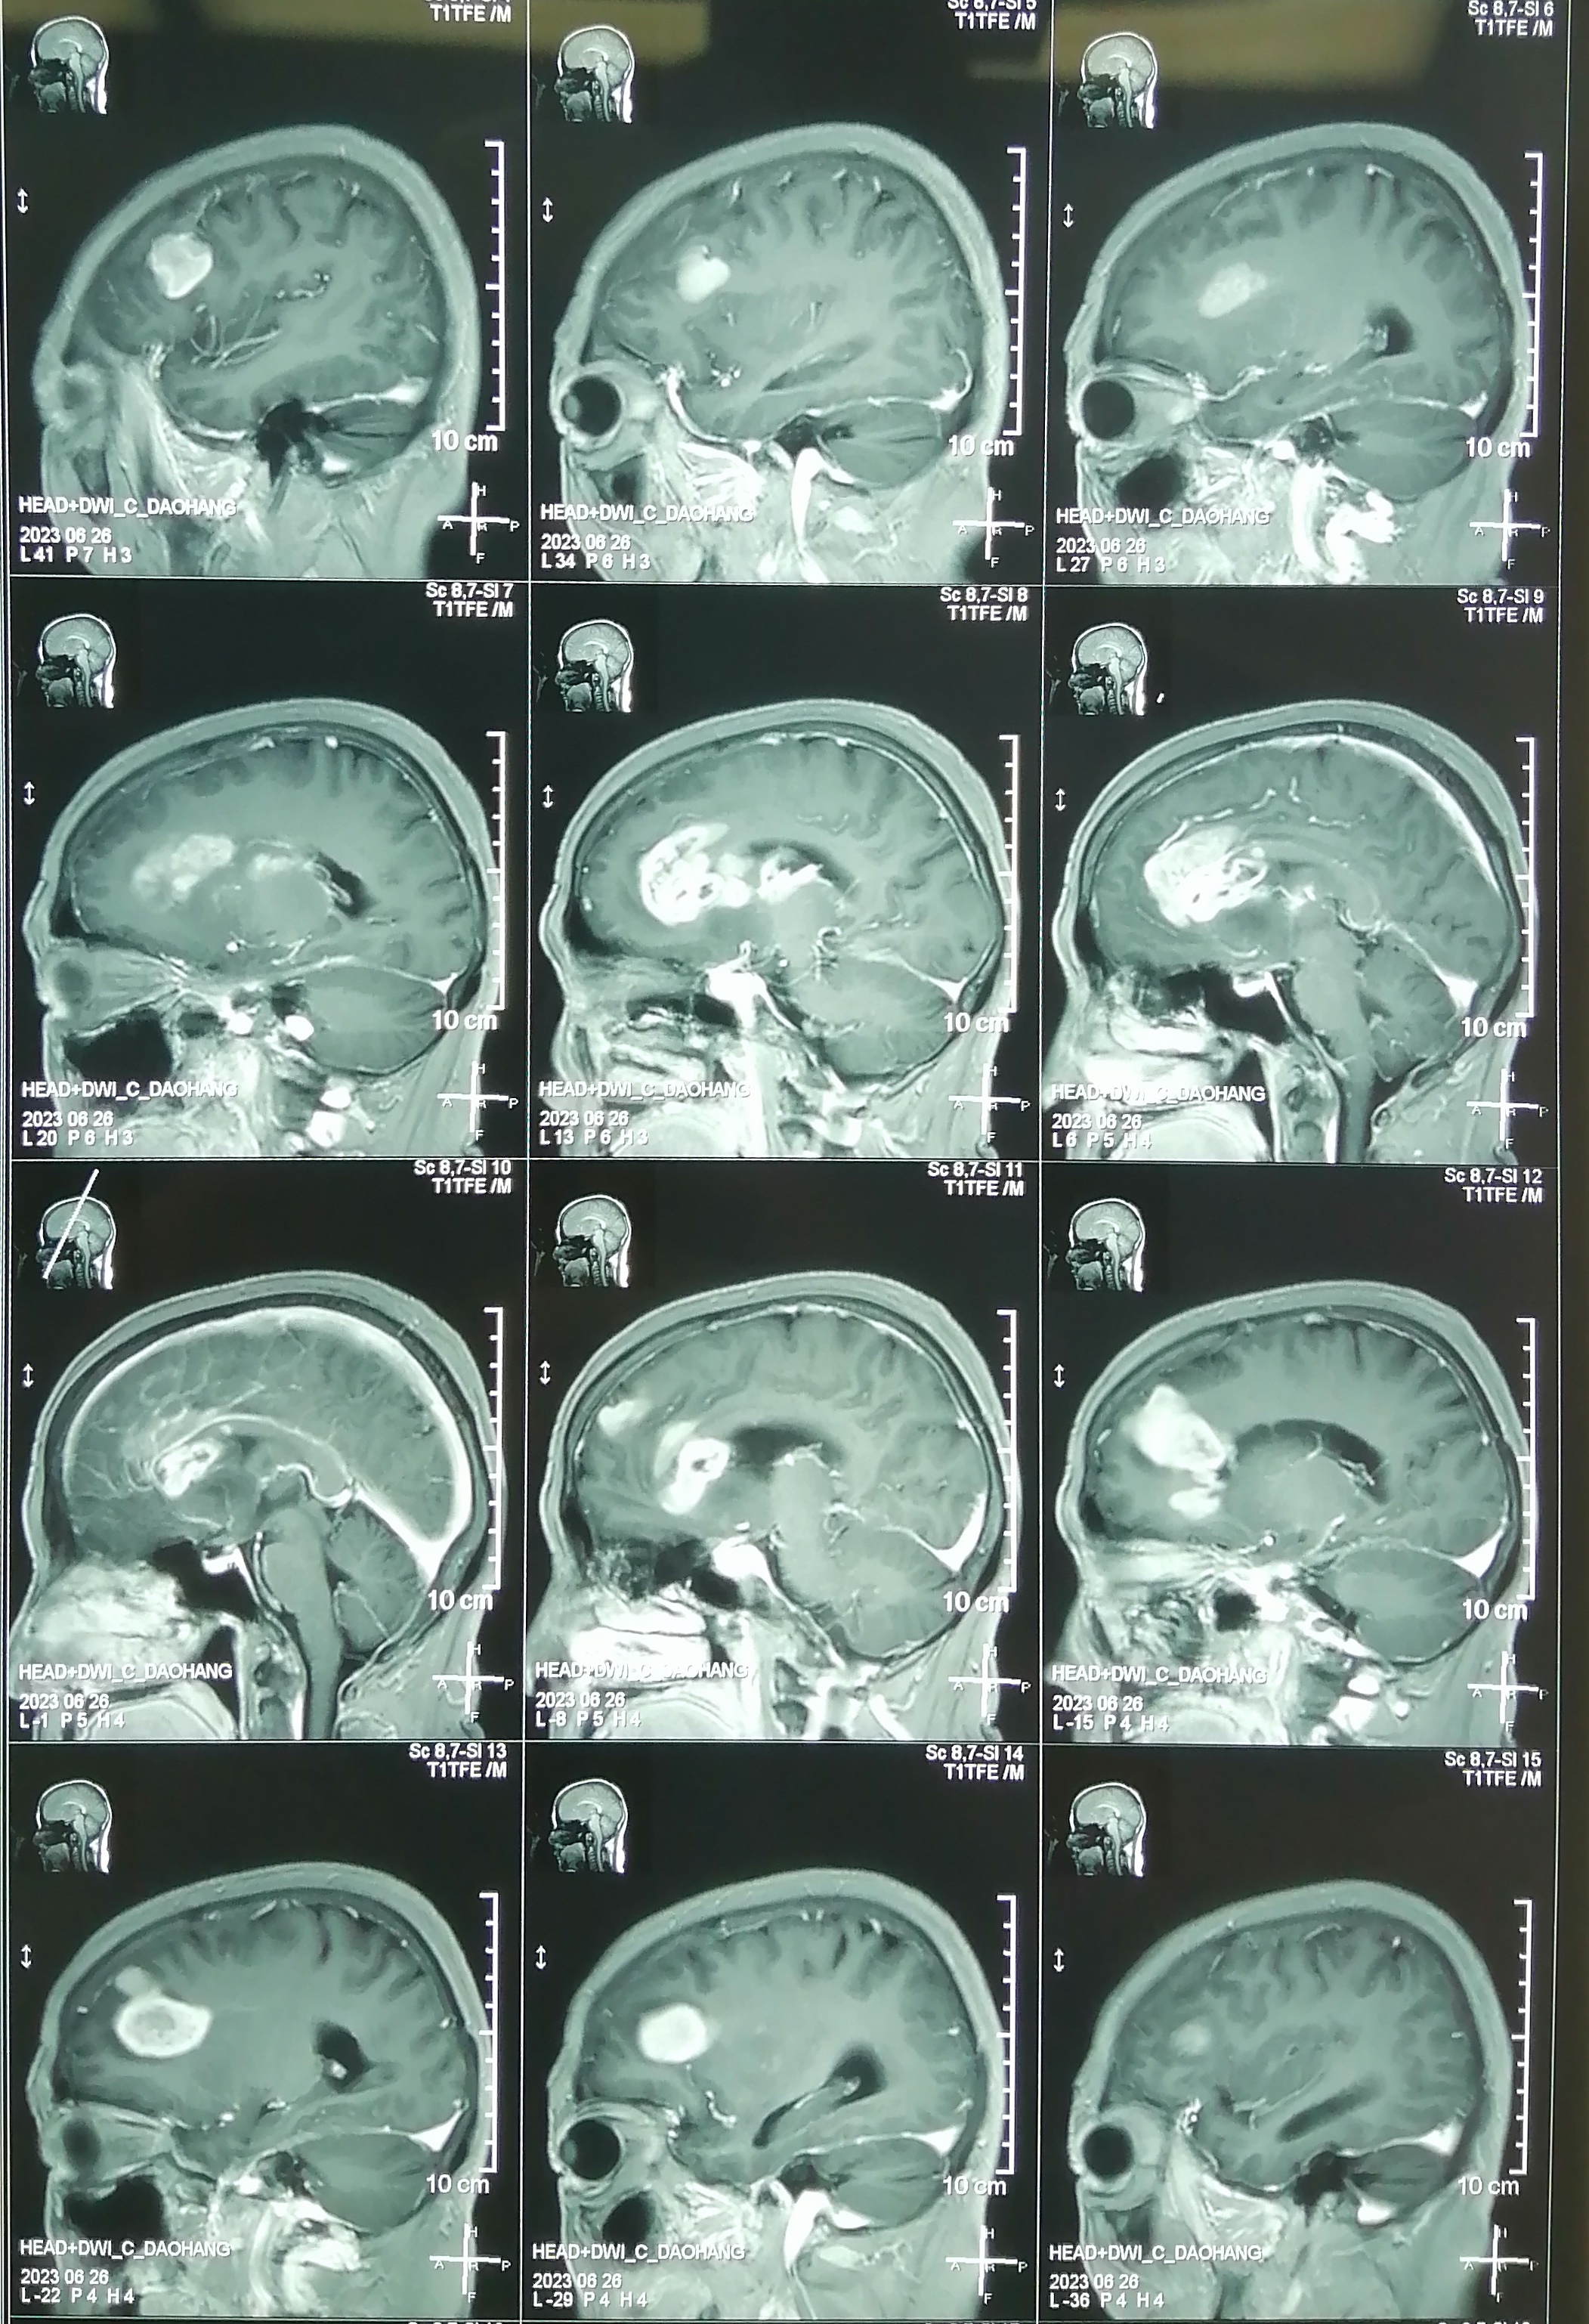

术前增强核磁:

片子可见肿瘤多中心, 累及范围广,包括胼胝体膝部,穹窿体,下丘脑,双侧额叶,左侧脑室前壁。